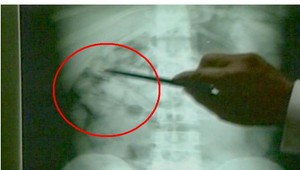

Tieto lieky sú určené najmä pre onkologických pacientov, ktorí trpia silnými bolesťami. Jeden z liekov patrí medzi najsilnejšie omamné látky a je vlastne náhradou morfínu. Mladík ich chcel ale pravdepodobne predať drogovo závislým. Podľa lekárničky sú jeho účinky porovnateľné s účinkami heroínu. Vedúca lekárne Eva Kulichová vysvetľuje: "Vyhľadávajú ho najmä tí zdraví ľudia, ktorí sú návykovo závislí na omamných látkach, pretože je silno halucinogénny."